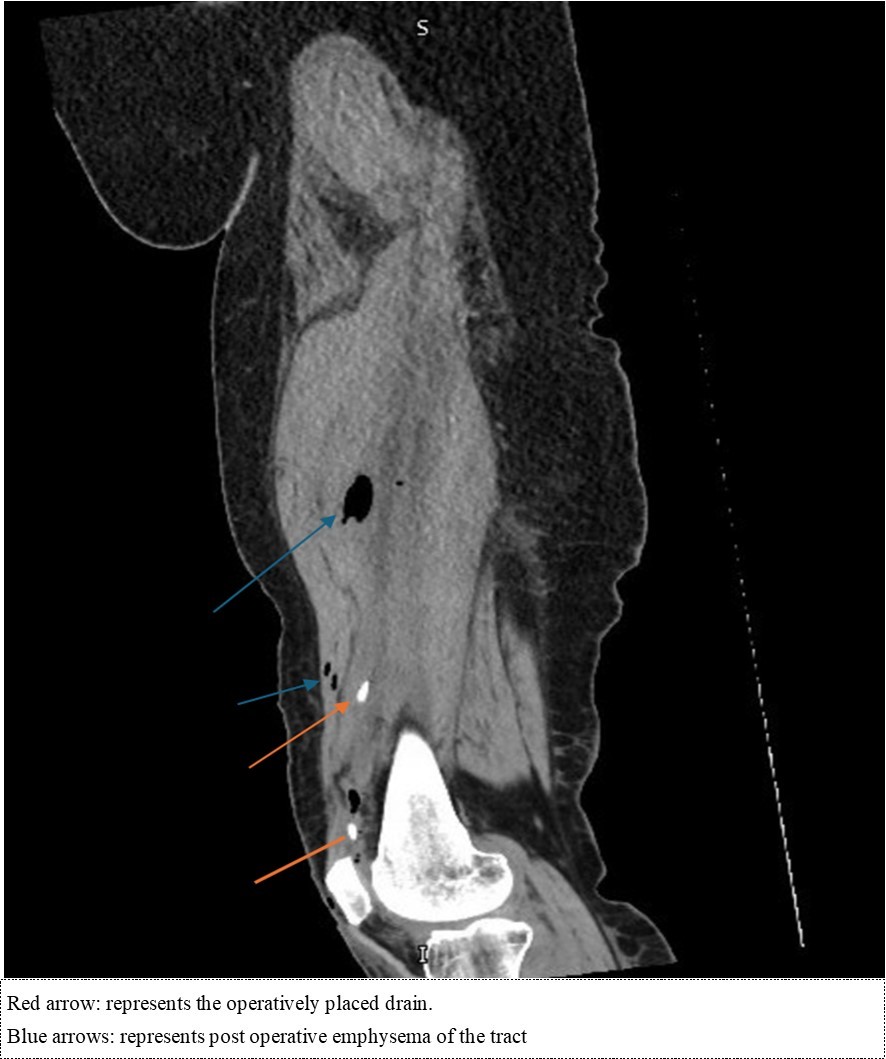

52-year-old female known to have traumatic brain injury (TBI) since the 1980’s with associated tremors and no other medical comorbidities had been complaining of right sided knee pain for multiple years. She notes that due to the tremors from her TBI, she had been deviating a lot of weight over her right side. However, for 6 months, the patient had been complaining of worse than usual right knee pain, for which she had been referred to the sports medicine clinic by her primary care physician. In the clinic, intra-articular joint injection (IJI) without ultrasound guidance was discussed and performed. 6 days following the joint injection, she had noted significant worsening of her knee pain with associated swelling and systemic symptoms including fevers and night sweats. She had presented to the emergency department. Lab work revealed a C-reactive peptide levels of 467.3 mg/L, a white blood cell count of 15.2x103 u/L and erythrocyte sedimentation rate of mm/hr. Arthrocentesis was performed with purulent material extracted, negative crystals, and notable for 175,0000 nucleated cells with 98% polymorphonucleated cells. She was started on linezolid 600 mg twice daily and taken for an operative knee washout. During the operation, a tract was noted to extend from the joint capsule to the lateral aspect of the thigh. External pressure to the lateral thigh was used to express purulent material through the tract, then an incision and drainage was performed to ensure complete extraction of the purulent matter with drain placement. CT scan of the right femur and knee without contrast was then performed following the operation (Figure 1a. and Figure 1b).

Figure 1a.Sagittal cut of the non-contrasted CT of the femur – soft tissue

Figure 1b.Coronal cut of the non-contrasted CT femur – soft tissue